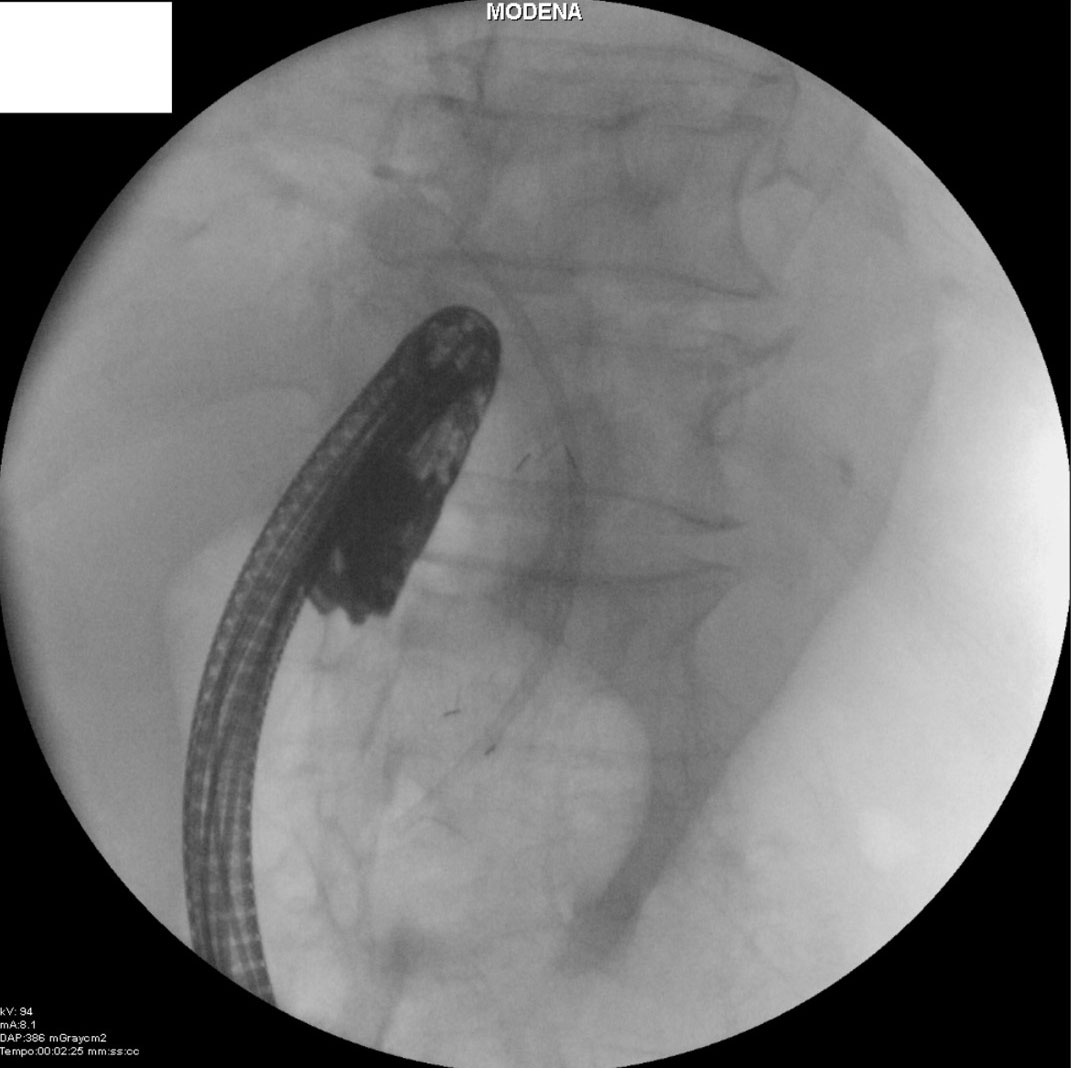

Early adverse events were: One duodenal bleeding due to tumor infiltration (procedure-related, mild severity), which was endoscopically treated with epinephrine injection and electrocautery, and one case of acute pancreatitis (stent-related, moderate severity) in a patient suffering from pancreatic cancer that was conservatively treated with an extended hospitalization (total 13 d). Treatment was not effective in 2 patients due to tumor overgrowth causing recurrent biliary obstruction, which occurred 3 month after the first procedure (stent occlusion rate 6.6%—time to stent occlusion was 94.5 ± d); both patients were treated with endoscopic placement of a co-axial plastic stent (Figure 5).

Figure 5

Figure 5. Recurrent biliary obstruction treated with placement of a co-axial plastic stent.